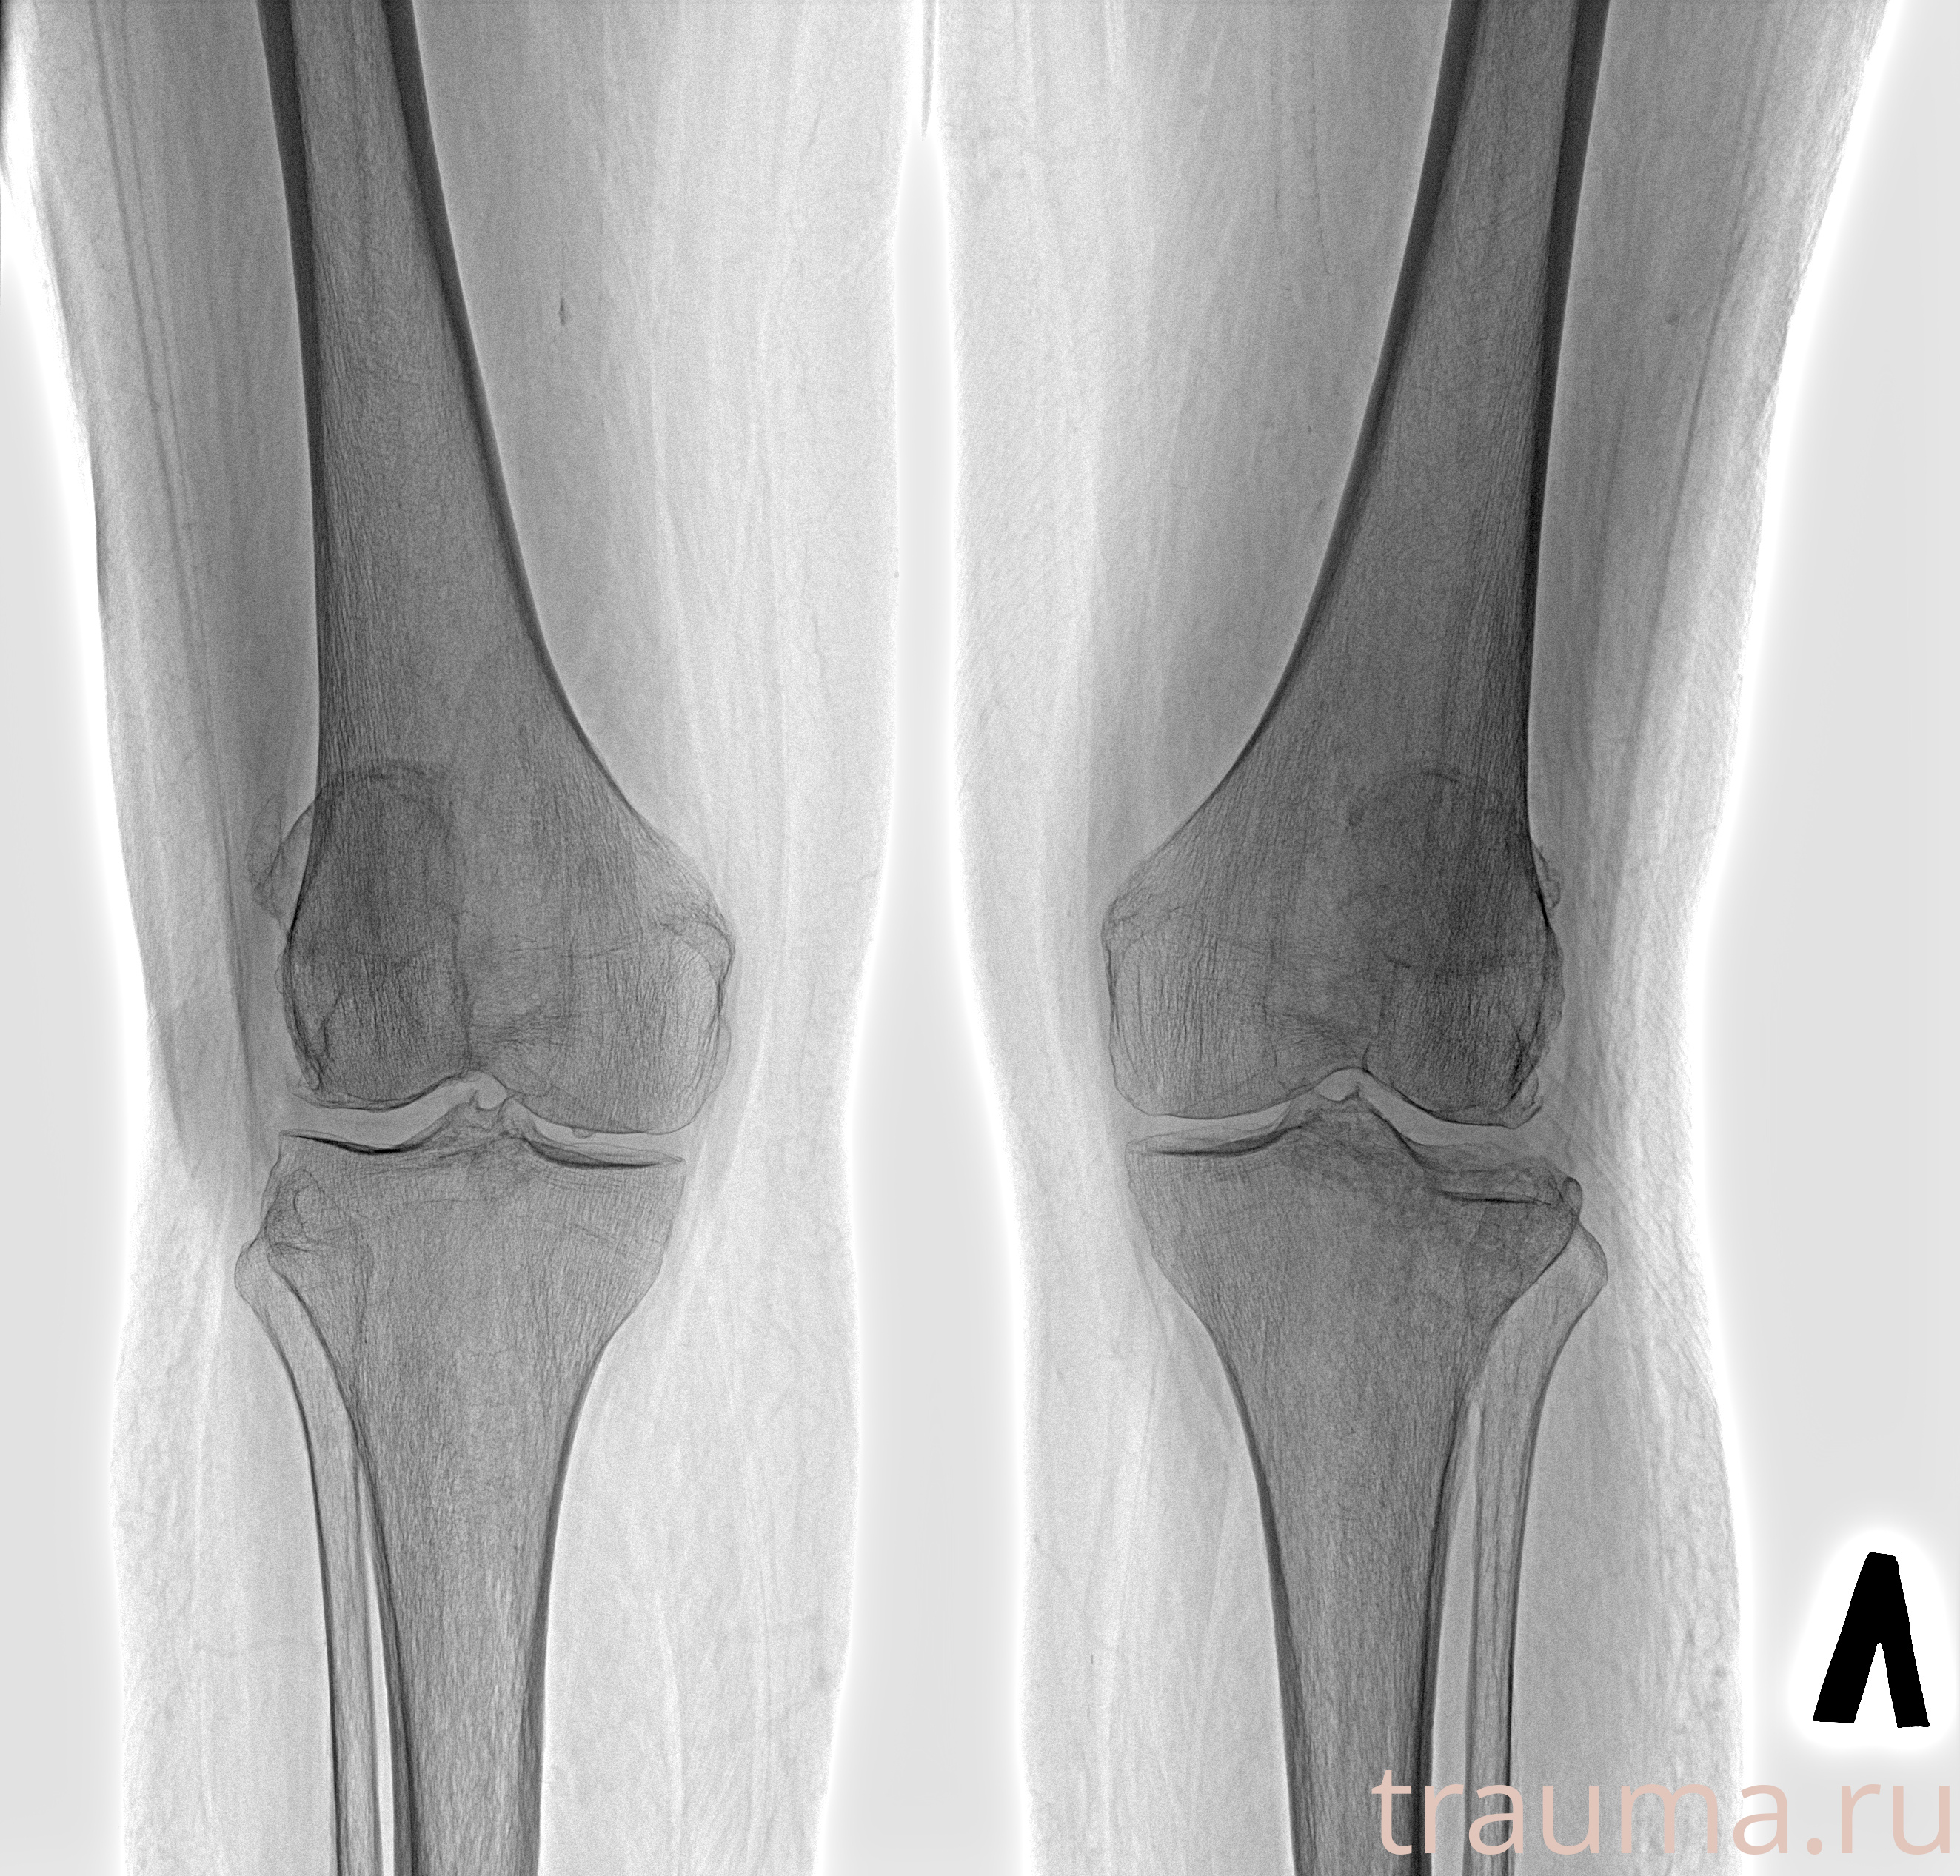

Рентгенограммы